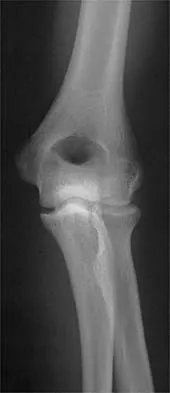

Question 38 High Yield

A 65-year-old woman fell onto her outstretched right arm and immediately had pain. She has a history of osteoporosis. Examination of the right arm reveals lateral arm swelling, ecchymosis, and she is unable to move the elbow due to pain. Her neurovascular status is intact. Radiographs are shown in Figures 14a and 14b. Appropriate treatment should include

Detailed Explanation

Comminuted, displaced radial head fractures (Hotchkiss type 3) require anatomic metallic radial head arthroplasty to regain function. Radial head excision has led to catastrophic sequelae including chronic wrist pain, elbow instability, and proximal radius migration. Immobilization, internal fixation, or anconeus arthroplasty are not recommended at this time because of the potentially poorer outcomes. Hotchkiss RN: Displaced fractures of the radial head: Internal fixation or excision? J Am Acad Orthop Surg 1997;5:1-10.